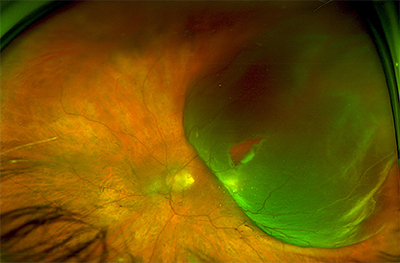

ophtavalmy.frFond D’oeil_Décollement Rétine Supérieur Avec Déchirure Rétinienne

ophtavalmy.frFond D’oeil_Décollement Rétine Supérieur Avec Déchirure Rétinienne